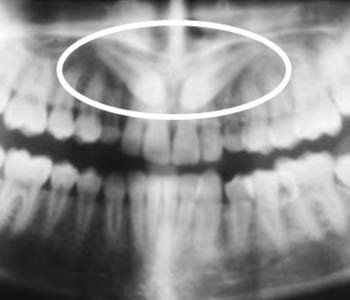

Crowding

There is not enough room in the mouth for all of the teeth to fit so they force space making teeth 'crowd'